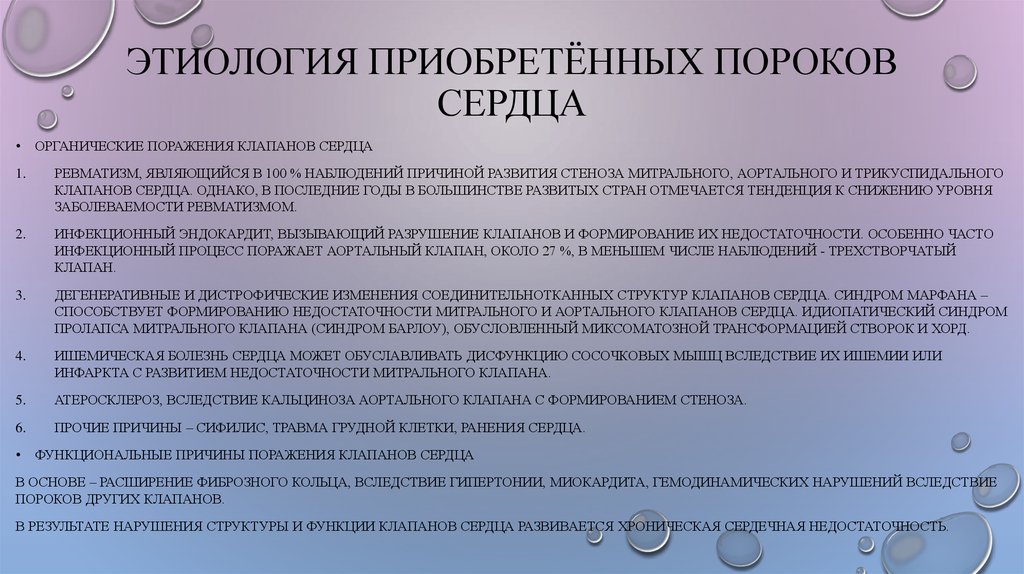

Фотографии и информация о приобретенных пороках сердца